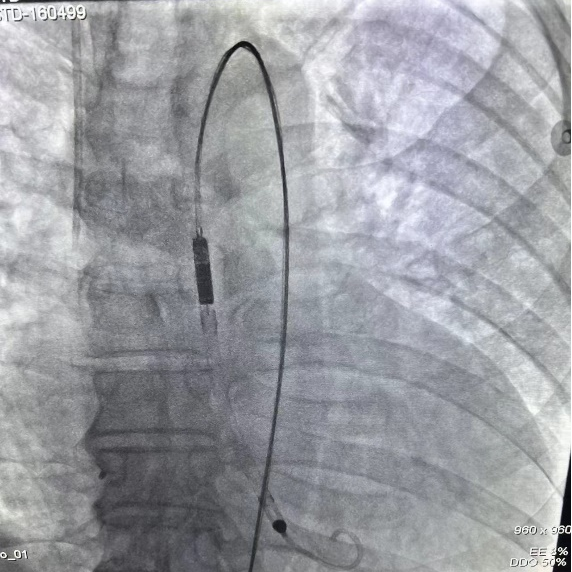

董念国教授团队经全方面评估和多学科会诊后,决定为患者实施经皮心室辅助装置植入手术,改善患者血流动力学。手术采用微创介入方式,顺利经股动脉入路,沿导丝将泵血装置送入左心室,部分替代心脏泵血功能,维持患者血液循环。手术过程顺利,患者平稳转至ICU。

D-Omniheart植入左心室影像